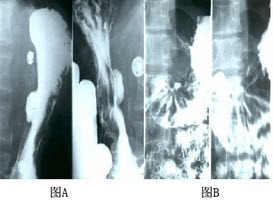

男性,55岁,上腹隐痛约十年,请做出正确诊断()

A、胃小弯胃癌

B、胃小弯胃溃疡

C、胃十二指肠溃疡

D、胃十二指肠癌

E、以上都不对

B